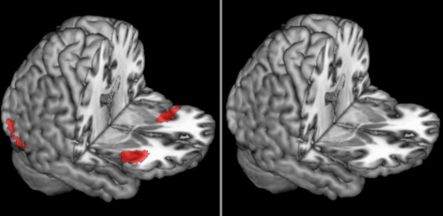

These images show that the bilateral anterior insula is more active for younger adults (left) as compared to older adults (right) when subjects are judging the trustworthiness of faces. Images provided by UCLA.